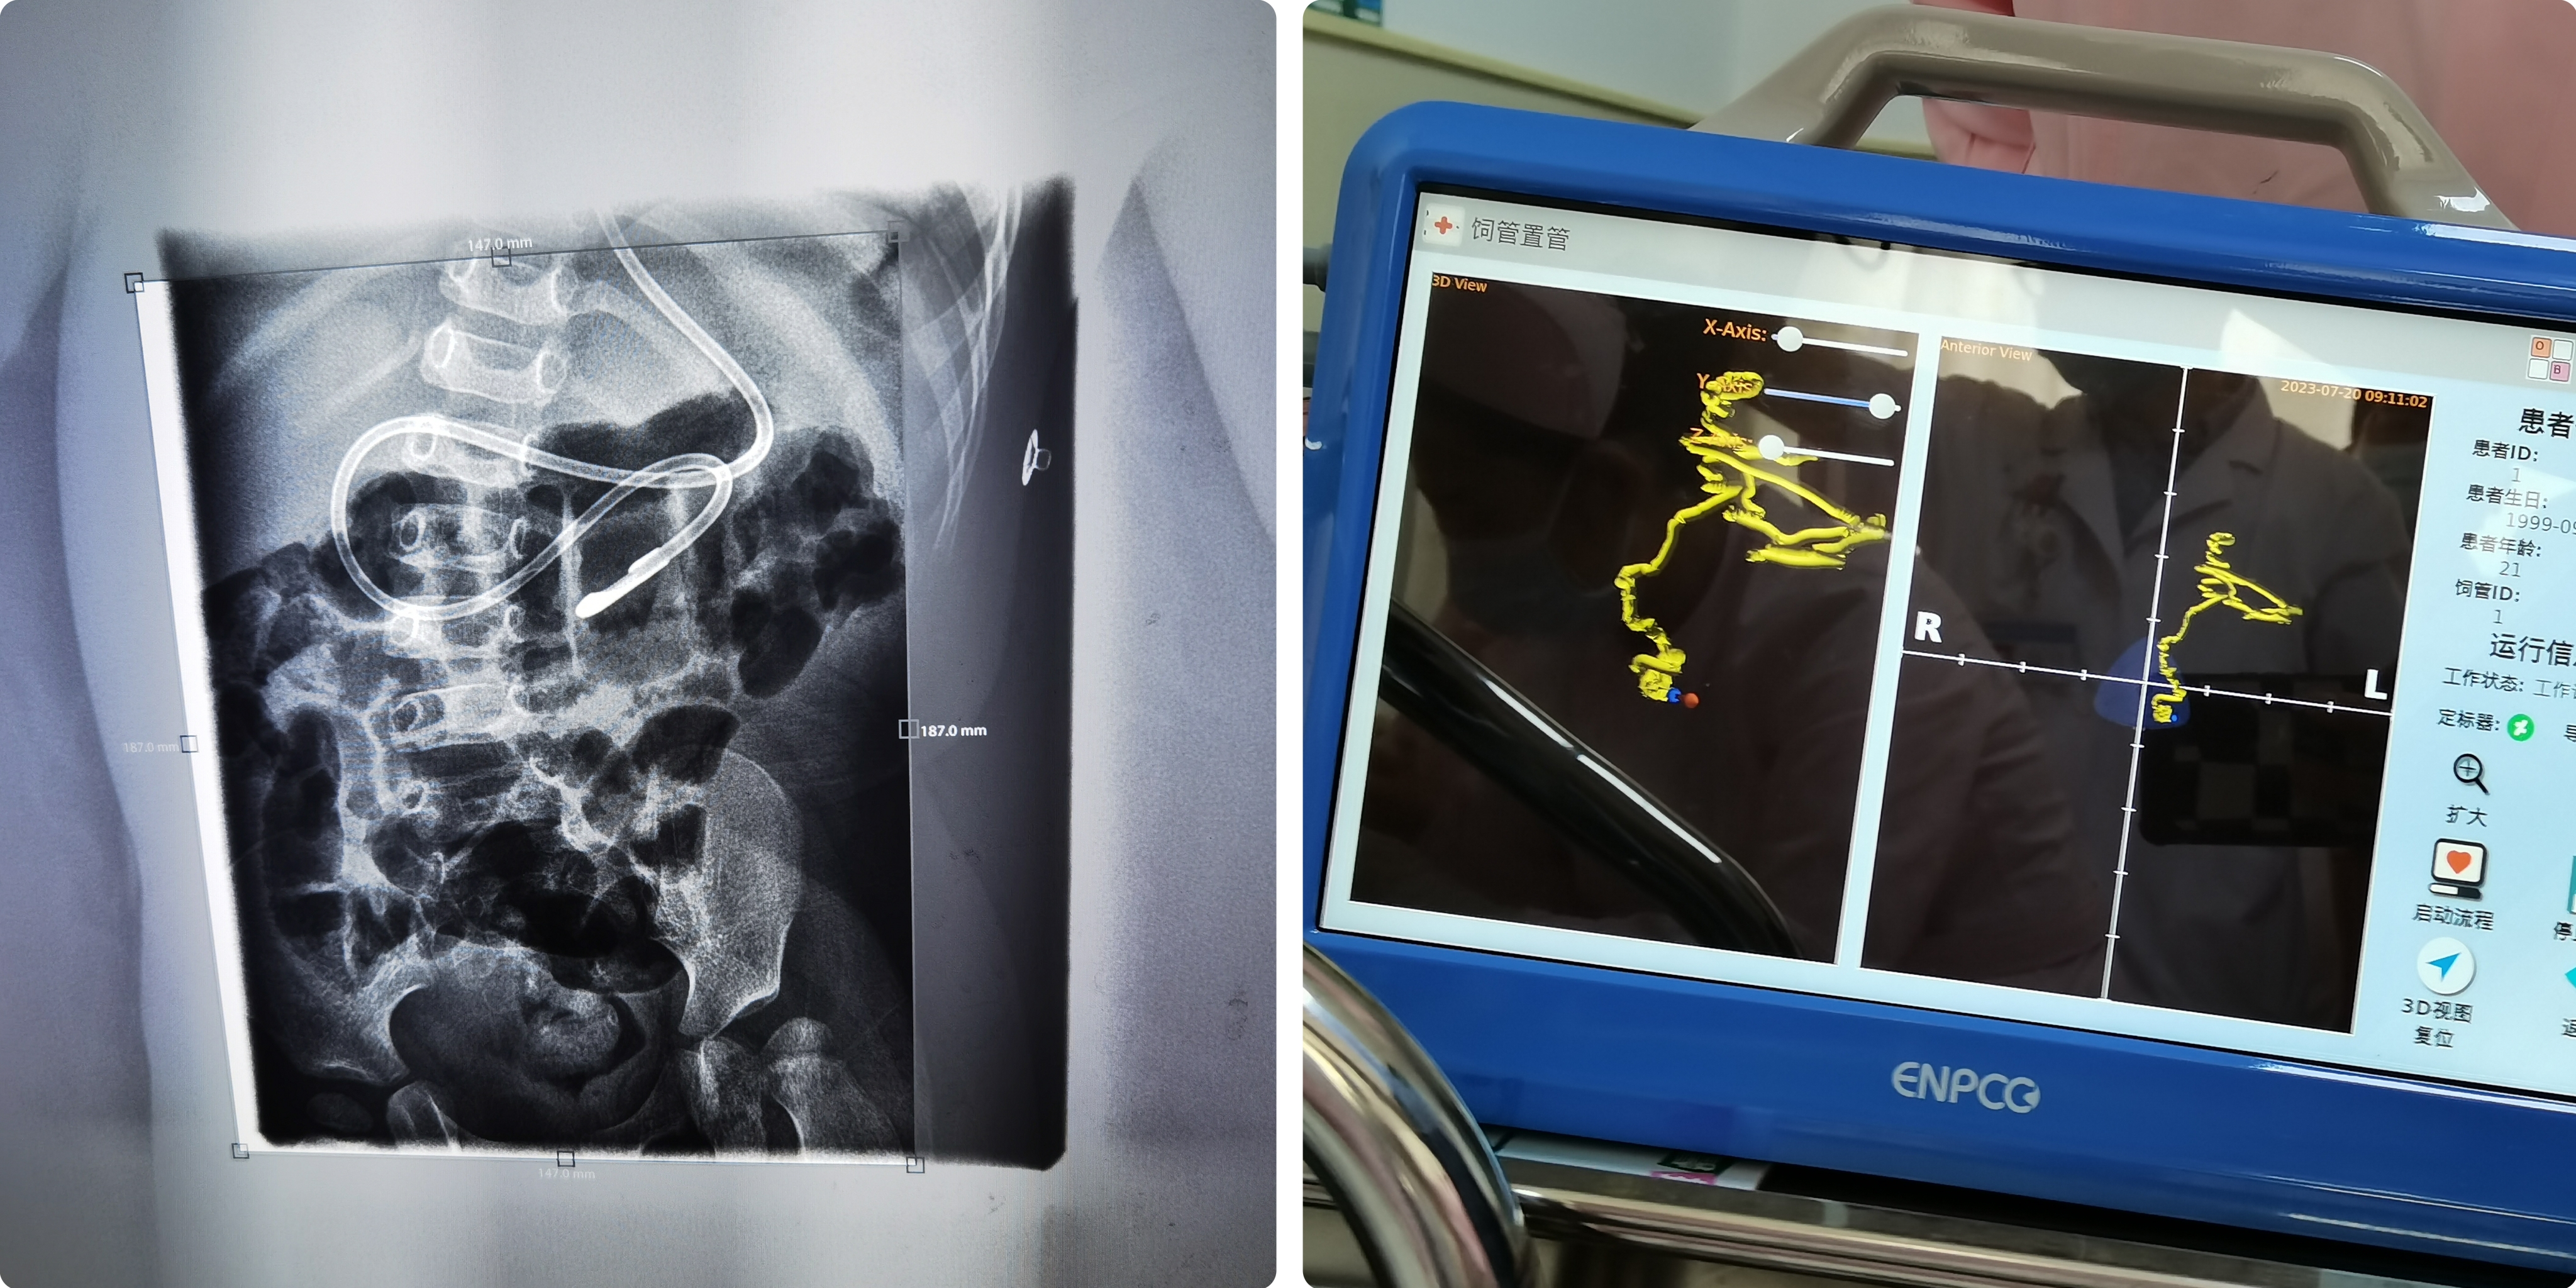

近日,郑州大学第三附属医院(河南省妇幼保健院)康复医学科二病区在医护共同努力下,开展了一项康复护理新技术——床旁徒手盲插鼻空肠管置管技术,为患儿的营养支持开辟了新渠道,成功解决了一例意识障碍患儿的营养难题。

这是一名溺水后意识障碍患儿,1岁11个月,入住康复医学科二病区之后,给予综合康复及对症支持治疗3疗程,患儿意识有所好转,给予鼻饲饮食,但问题频发,每日吐奶大于3次,在呕吐时总是出现胃管移位问题,增加了误吸的风险,给予饮食指导后疗效不佳。此时儿科营养筛查评分为3分,经医生评估,存在中度营养不良风险,且孩子体重不断下降,家长十分担忧患儿营养问题,经医护讨论决定给予鼻空肠管喂养。患儿异常哭闹和四肢肌张力高等问题给置管过程带来很大风险,在康复医学科主任朱登纳和护士长王瑞霞的慎重考虑下,决定由吞咽障碍专科护士贾岩岩执行此项操作,王瑞霞全程指导协助,最终顺利置管。几日后,患儿吐奶频率有所降低,营养不良状况得到改善,患儿家属对科室的治疗方案给予了充分的肯定。

康复医学科二病区徒手盲插鼻空肠管置管技术的开展为危重患儿带来了新的治疗方案,为患儿的营养提供了有力保障,也标志着护理技术得到了进一步的提升。